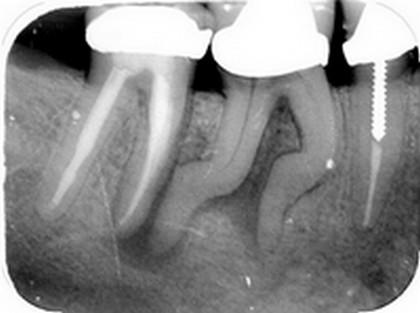

* Indepartarea tesutului vasculo-nervos (viu sau necrotic) din interiorul dintelui sau indepartarea unei obturatii de canal incorecte; * Dezinfectarea canalului radicular; * Largirea mecanica a canalului radicular; * Obturatia canalului radicular (umplerea si sigilarea canalului radicular cu gutaperca si pasta pentru sigilat); * Reconstituirea corono radiculara (metalica sau cu pivot din fibra de sticla).